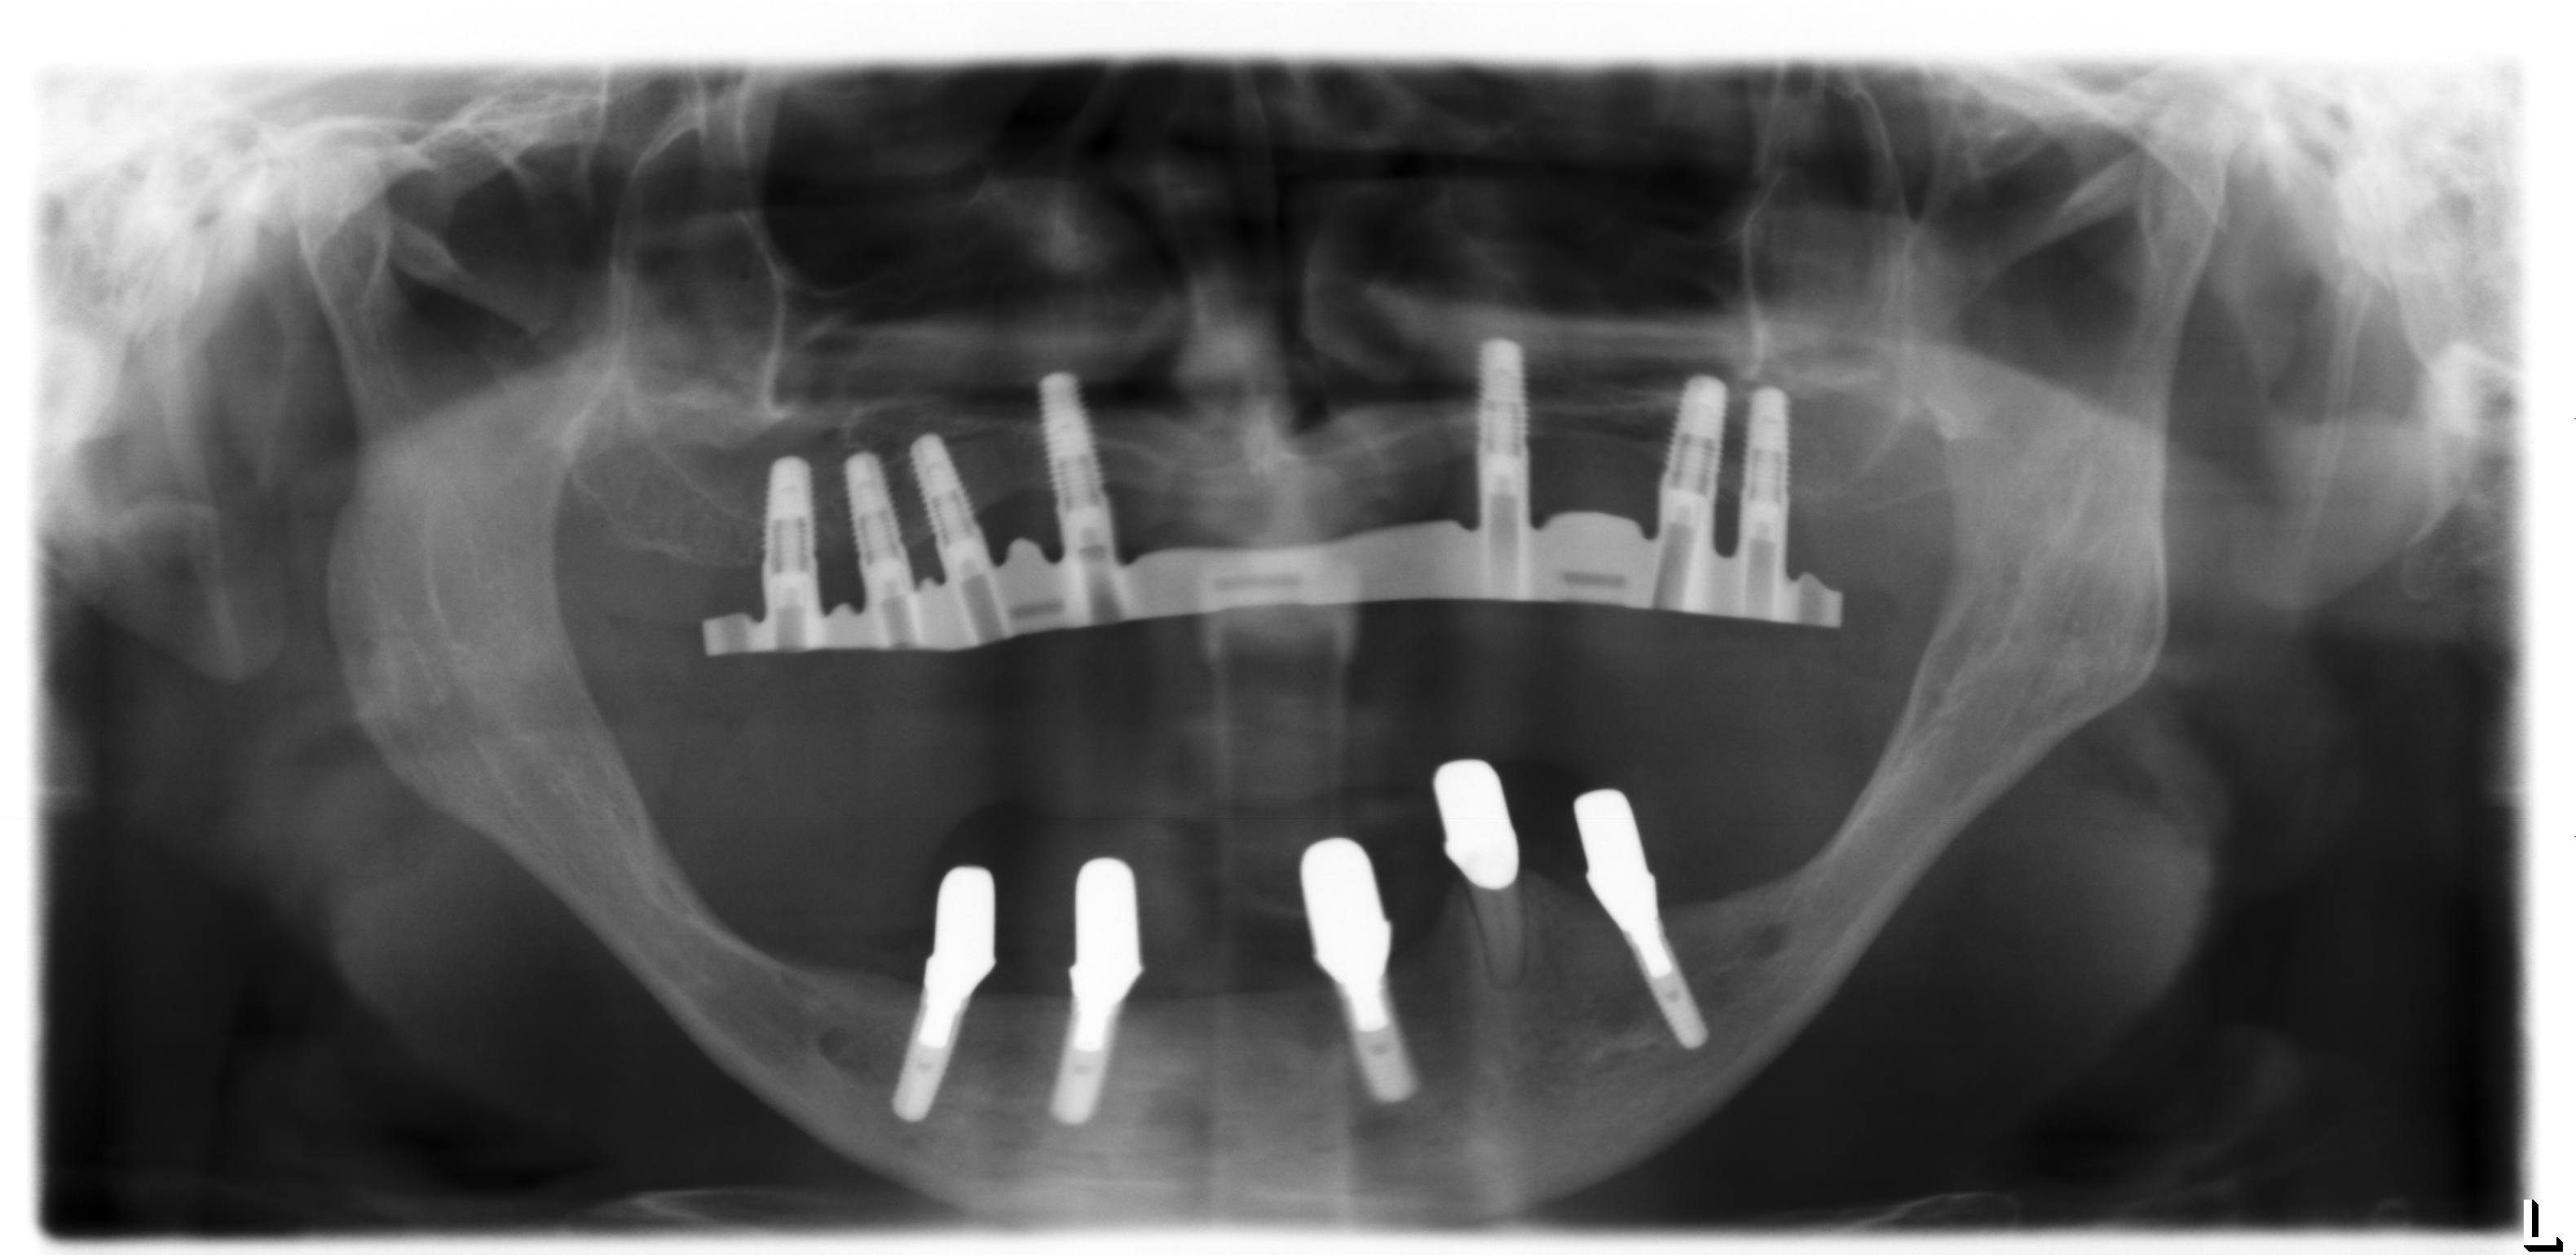

Für derart komplexe Fälle ist das interdisziplinäre Zentrum für Zahnärztliche Implantologie der Ansprechpartner: Der Patient wird in einer interdisziplinären Sprechstunde vorgestellt und die Planung des Patienten in dem interdisziplinär geleiteten Implanatboard erstellt. Anschließend erfolgt der Knochenaufbau in ITN. Dabei werden die angelagerten Knochenstücke über sogenannte Osteosyntheseplatten in den Bereichen fixiert, an denen später die Implantate gesetzt werden sollen (Abb.6). Zeitgleich erfolgte im Unterkieferbereich eine Nervverlagerung des Unterkiefernervs und im Oberkiefer eine Knochenaufbau im Bereich der Kieferhöhlen (sogenannter „Sinuslift“) (Abb.7). Nur durch diese ausgedehnten Augmentationsmaßnahmen ist ein späteres Einbringen der Implantate sinnvoll möglich. Vier Monate später erfolgt die Entfernung der Osteosyntheseplatten (Abb.8) in Kombination mit dem Setzen der Implantate (Abb.9). Die genaue Position der Implantate wird dabei über eine individuell hergestellte Schablone (sogenannte Bohrschablone) festgelegt (Abb.10).

Damit stellt man sicher, dass die Implantate hinterher auch an der richtigen Position stehen und den späteren Zahnersatz optimal unterstützen (Abb.11). Abschließend erfolgt die prothetische Versorgung des Patienten. Dazu werden die Implantate im Mund abgeformt (Abb.12) und mit Hilfe einer „Abformung“ auf ein Gipsmodell übertragen (Abb.13). Auf diesem wird anschließend die prothetische Versorgung hergestellt (Abb.14). In diesem speziellen Fall wurde für den Oberkiefer eine steggetragene Prothese (Abb.15, Abb.16) hergestellt. Dieser wird dann auf den Implantaten im Mund verschraubt (Abb.15) und darüber eine herausnehmbare Prothese (Abb.17) verankert (Abb.16).